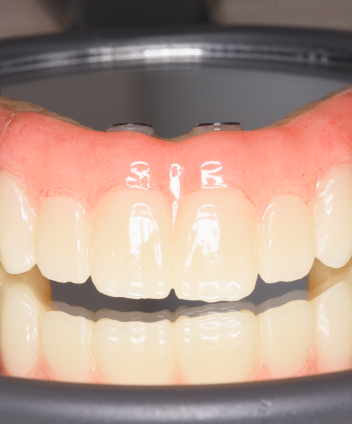

手術当日に仮歯を装着できる「即時荷重」に対応しており、

「手術をしたその日から食事や会話ができる」という大きなメリットがあります。

All-on-4の開発者のDr Pole Maroの咬合哲学と設計思想を忠実に守り、非純正パーツによる破損・不適合リスクを避け、長期的に安心して使える正規クオリティの治療を提供します。

デジタル精密設計×審美再建“美しく噛めるAll-on-4”

デジタル精密設計×審美再建

“美しく噛めるAll-on-4”

3DフェイススキャンやCT、口腔内スキャナーによる完全デジタルのフル設計と診断で歯と口元だけでなくお顔のバランスにも配慮した設計を提供しています。また術後のメンテナンスと清掃性を大切にして炎症や口臭トラブルを軽減します。